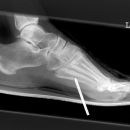

Nagel im Fuß